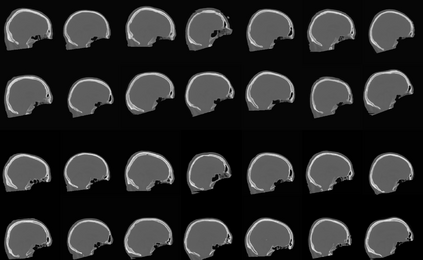

Model-based treatment planning for transcranial ultrasound therapy typically involves mapping the acoustic properties of the skull from an x-ray computed tomography (CT) image of the head. Here, three methods for generating pseudo-CT images from magnetic resonance (MR) images were compared as an alternative to CT. A convolutional neural network (U-Net) was trained on paired MR-CT images to generate pseudo-CT images from either T1-weighted or zero-echo time (ZTE) MR images (denoted tCT and zCT, respectively). A direct mapping from ZTE to pseudo-CT was also implemented (denoted cCT). When comparing the pseudo-CT and ground truth CT images for the test set, the mean absolute error was 133, 83, and 145 Hounsfield units (HU) across the whole head, and 398, 222, and 336 HU within the skull for the tCT, zCT, and cCT images, respectively. Ultrasound simulations were also performed using the generated pseudo-CT images and compared to simulations based on CT. An annular array transducer was used targeting the visual or motor cortex. The mean differences in the simulated focal pressure, focal position, and focal volume were 9.9%, 1.5 mm, and 15.1% for simulations based on the tCT images, 5.7%, 0.6 mm, and 5.7% for the zCT, and 6.7%, 0.9 mm, and 12.1% for the cCT. The improved results for images mapped from ZTE highlight the advantage of using imaging sequences which improve contrast of the skull bone. Overall, these results demonstrate that acoustic simulations based on MR images can give comparable accuracy to those based on CT.